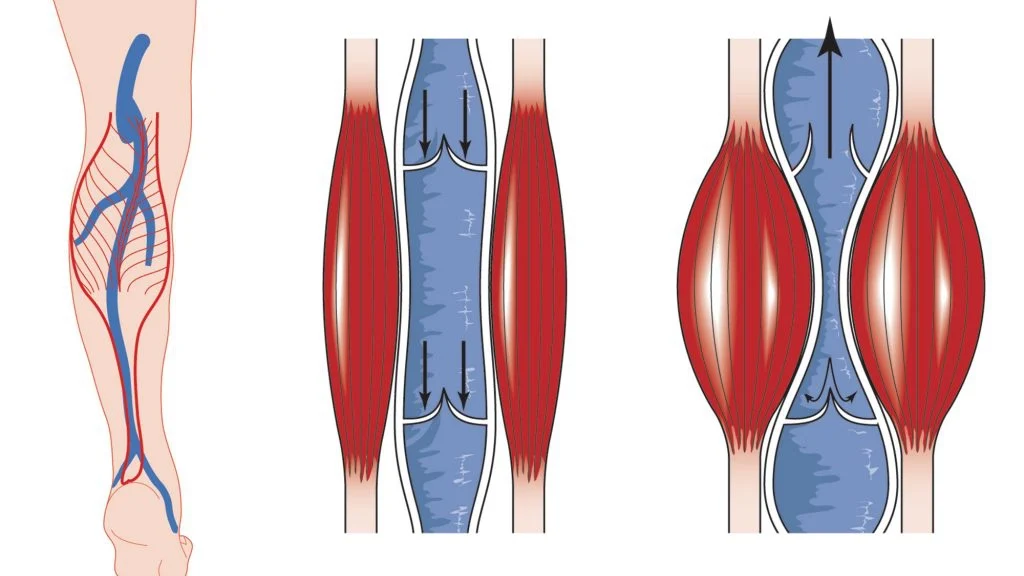

2. Kraujotakos sutrikimai

- Sumažėjusi kraujotaka į vidinės ausies struktūras gali lemti garsinės informacijos perdavimo sutrikimus.

- Venų stazė galvos srityje, atsirandanti dėl kaklo kraujagyslių suspaudimo, gali sukelti pulsuojantį tinitą.

3. Kraujotakos sutrikimai – „pulsuojantis tinitas“

- Esant kraujotakos sutrikimams galvos srityje, dažnai pasireiškia pulsuojantis ūžesys, kuris sinchronizuojasi su širdies ritmu.

- Venų stazė (užsikimšusios arba neefektyviai dirbančios kraujagyslės).

- Padidėjęs kraujospūdis, sukeliantis vidinės ausies kraujotakos pokyčius.

- Slankstelinės arterijos suspaudimas dėl laikysenos ar raumenų įtampos.

2. Kraujotakos gerinimo poveikis tinitui

- 2020 m. atliktas tyrimas (Cagnie et al.) įrodė, kad manualinė terapija kartu su kraujotaką gerinančiais metodais (pvz., miofascialiniu atpalaidavimu) pagerino vidinės ausies kraujotaką ir sumažino tinitą 72 % pacientų.

- Geresnis kraujo pritekėjimas į slankstelines arterijas leido sumažinti pulsaciją ir pagerinti klausos sistemos funkciją.